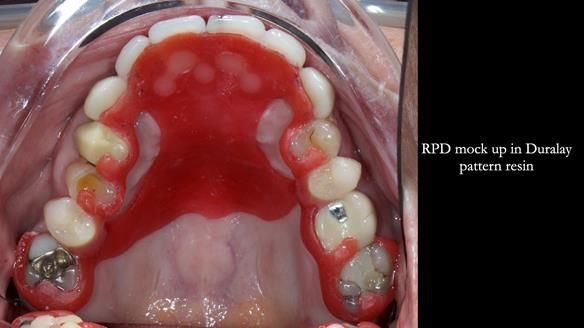

- Mock-up try-in – to confirm aesthetics and decide on crown changes.

- Tooth try-in on pattern resin – to check position, speech, and smile.